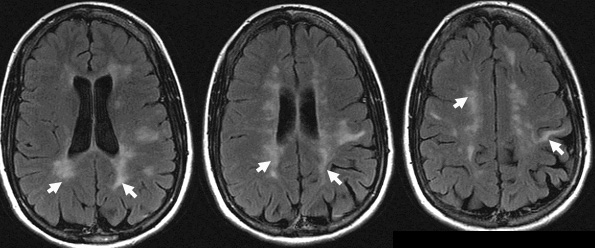

Nonenhanced brain MRI (FLAIR) images show asymmetrical, abnormal high signal white matter lesions in the periventricular and subcortical areas

They are seen as bright lesions on T2 weighted or FLAIR series MRI.

Multiple sclerosis plaques occur in the white matter of the cerebral hemispheres, brain stem and spinal cord.